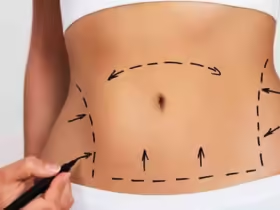

حذّرت دراسة جديدة من خطر صحي مثير للقلق يرتبط بتراكم الدهون في منطقة البطن، التي تضم أعضاء مثل الكبد والبنكرياس.

وفي الدراسة، فحص الباحثون البيانات الصحية لأكثر من 32 ألف بريطاني (متوسط أعمارهم 55 عاما)، حيث خضع كل مشارك لفحص التصوير بالرنين المغناطيسي لبطنه لقياس كمية الدهون حول الأعضائه الداخلية مثل الكبد والبنكرياس، والمعروفة طبيا باسم الدهون الحشوية.

وقاس فريق البحث أيضا كمية الدهون الموجودة تحت الجلد مباشرة.